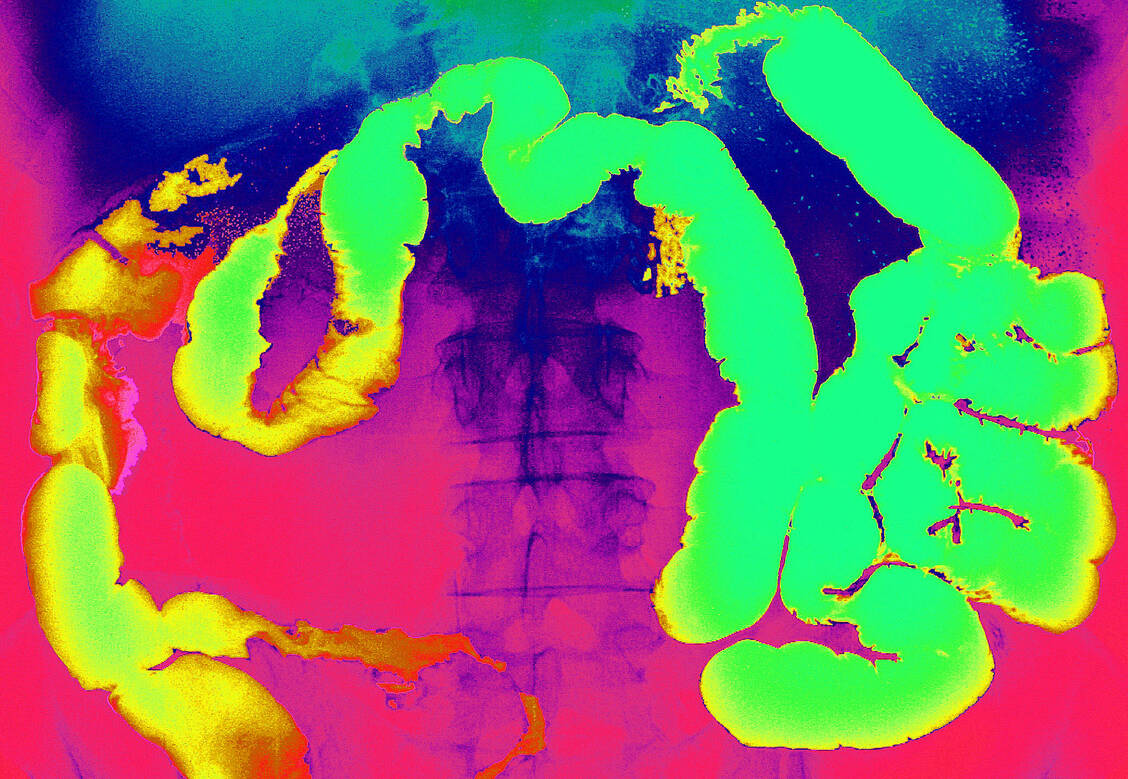

Zu den chronisch entzündlichen Darmerkrankungen (CED) zählen Morbus Crohn und Colitis ulcerosa. Während Letztere in der Regel im Enddarm beginnt und von dort aus meist kontinuierlich unterschiedlich weit in den Dickdarm hineinreicht, kann die Entzündungsreaktion bei Morbus-Crohn-Betroffenen den gesamten Verdauungstrakt betreffen – von den Lippen bis zum Darmausgang. Besonders häufig reagiert der Übergang zwischen Dick- und Dünndarm. Beide Erkrankungen treten häufig erstmals bereits bei jungen Menschen auf und nehmen in den vergangenen Jahren in Ländern mit westlichem Lebensstil stetig zu.